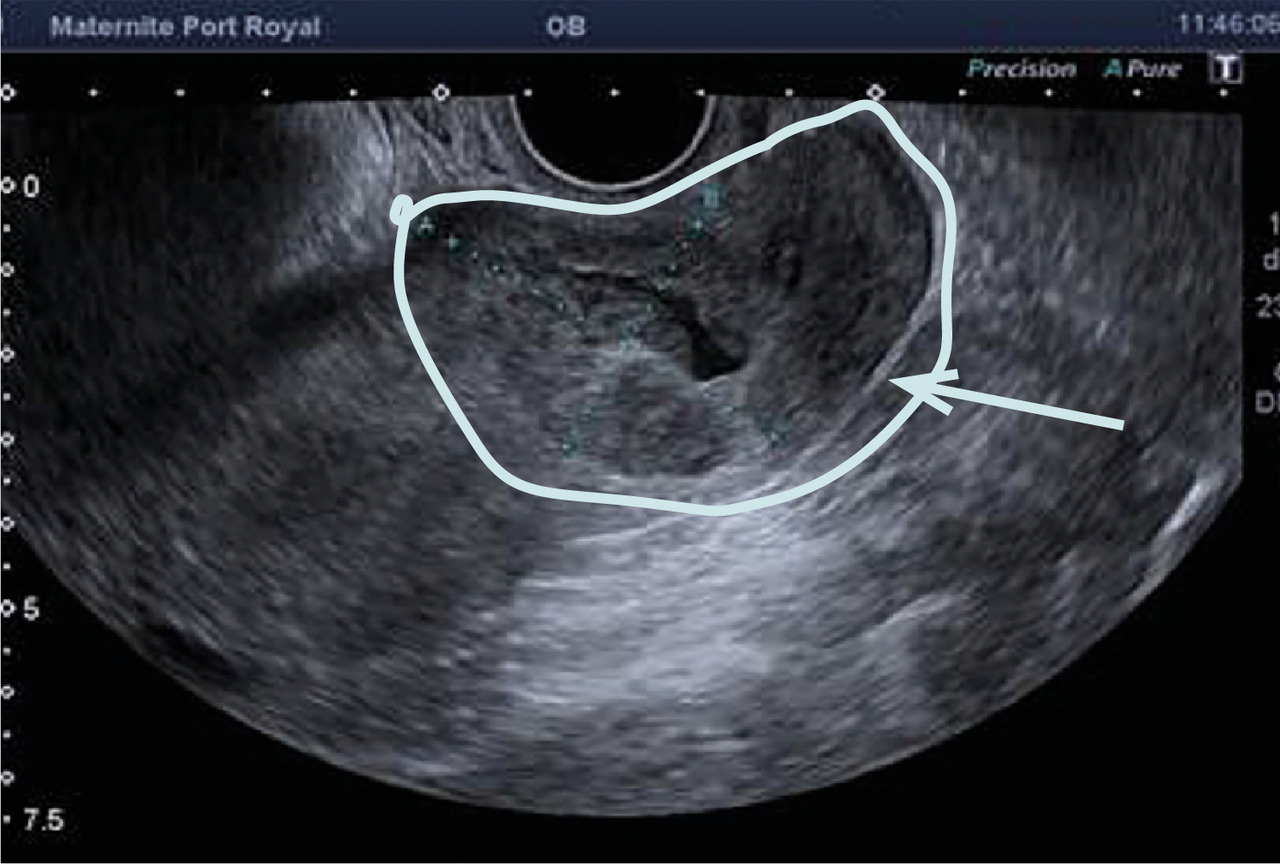

L’échographie, indispensable, doit examiner le pelvis mais aussi l’abdomen. Elle est donc réalisée par voie endovaginale, sus-pubienne et abdominale. On peut visualiser une masse latéro-utérine (fig. 1). Au sein de cet hématosalpinx, un sac gestationnel peut être visible, voire un embryon (fig. 2) ayant parfois une activité cardiaque positive. Le passage de la sonde à ce niveau est douloureux.

Souvent, le principal signe est indirect :

– vacuité utérine (fig. 3) et taux de hCG supérieur à 1 500 UI/L, fortement évocateurs. En cas de métrorragies, une lame d’hématométrie peut être visible en intra-utérin (« pseudo-sac gestationnel » : image hypo-échogène centrée dans la cavité, sans couronne trophoblastique) ;

Remerciements au Dr Gilles Grange, maternité Port-Royal, Paris pour les figures 1, 2 et 3.